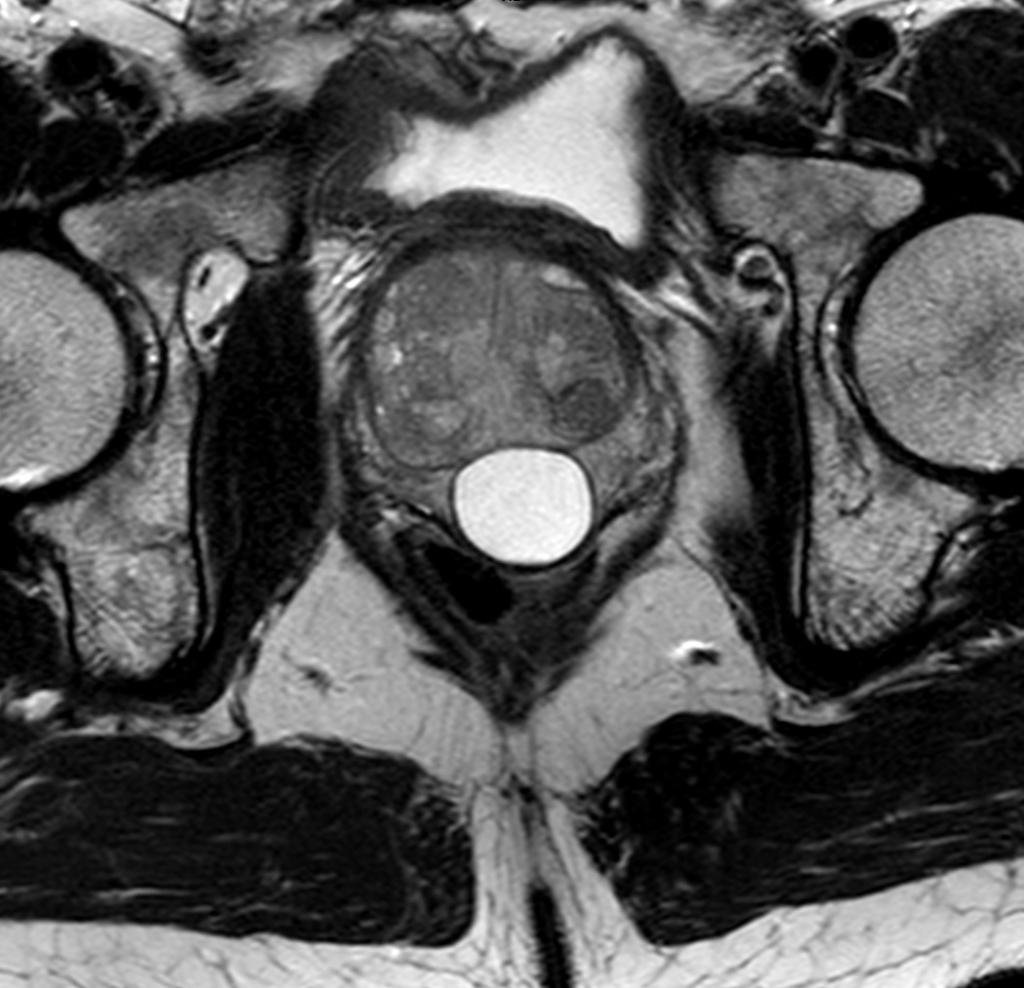

Bij een 64-jarige man met mictieklachten (‘lower urinary tract symptoms’, LUTS) wordt bij rectaal toucher een caudaal gelegen, gladde nodus gevoeld in de mediaanlijn van de prostaat. Uroflowmetrie, bepaling van het urineresidu en de PSA-waarde laten geen afwijkingen zien, MRI van de prostaat echter wel. Wat is uw diagnose?